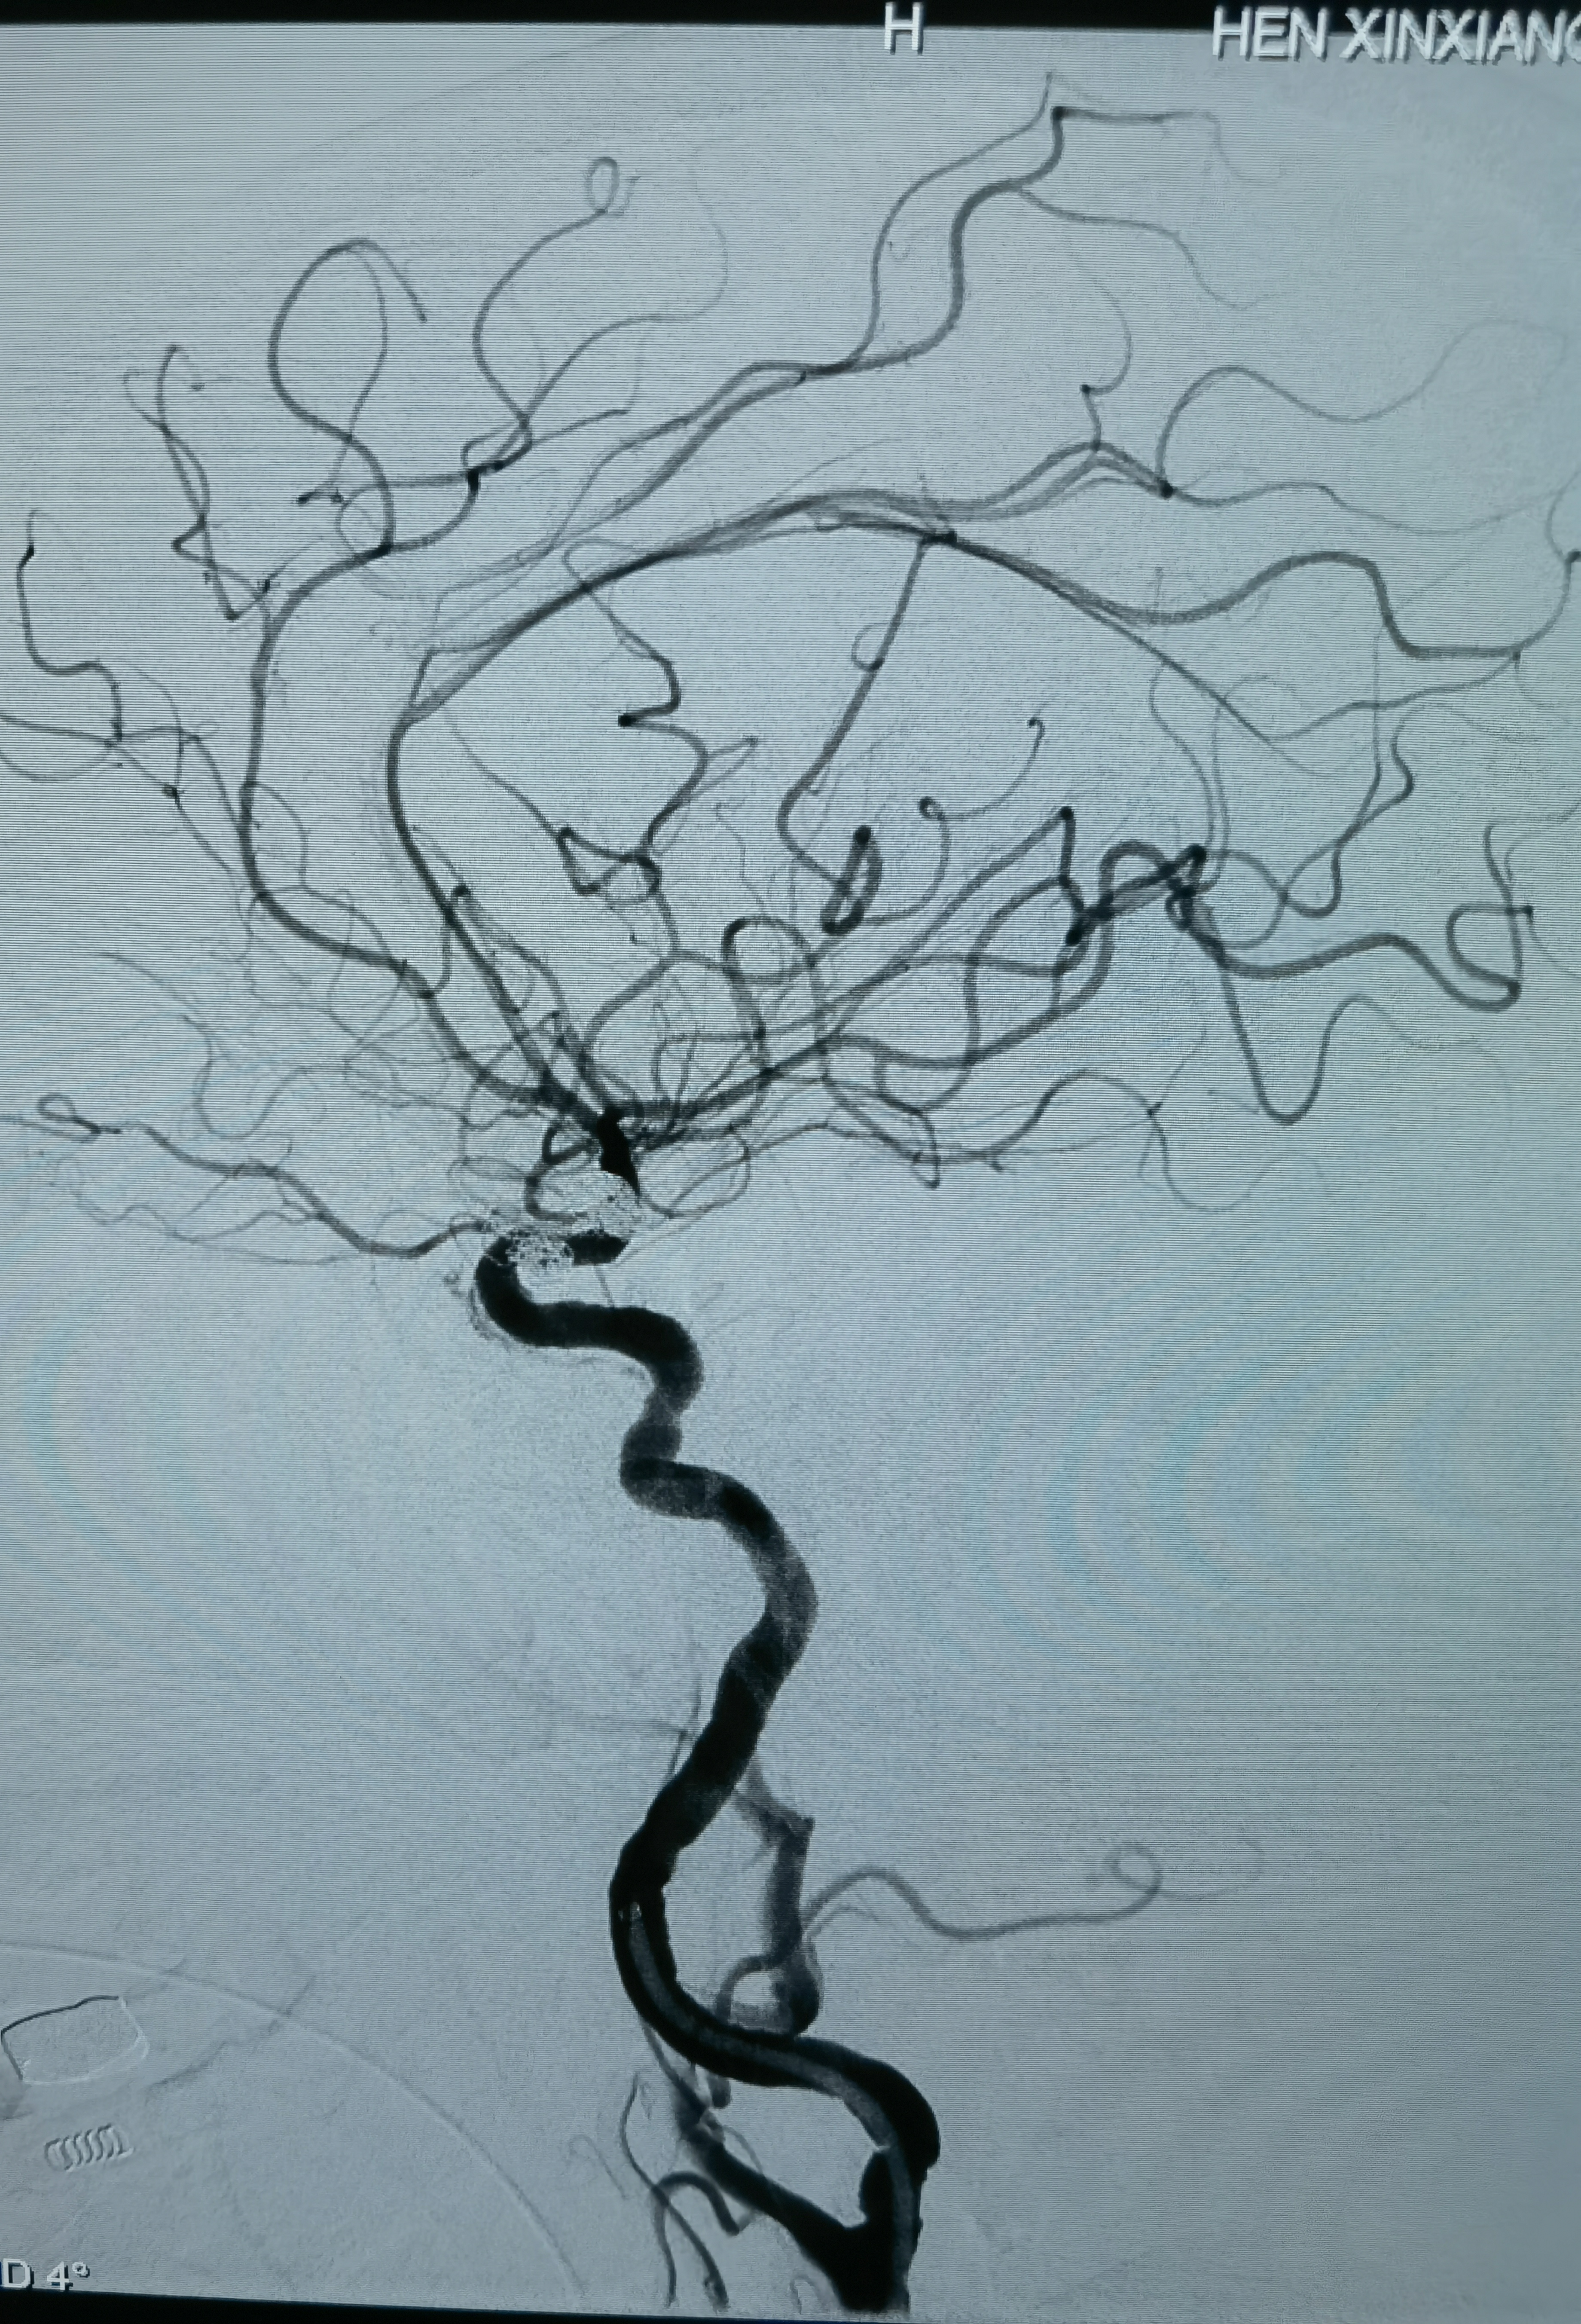

术后正位造影

术后侧位造影